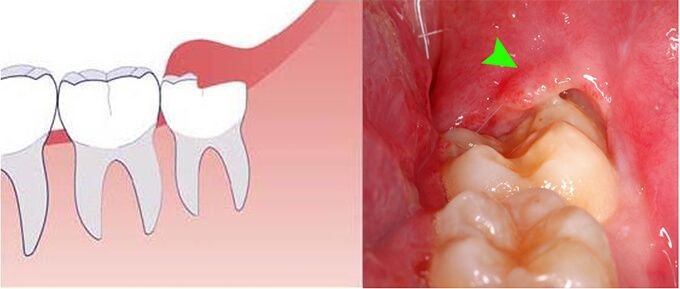

Thông thường, viêm lợi trùm thường xuất hiện ở răng khôn hàm dưới, và tình trạng này có thể ảnh hưởng nghiêm trọng đến sức khỏe răng miệng cũng như dễ phát sinh nhiều biến chứng nguy hiểm. Viêm lợi trùm xảy ra do cung hàm bị thiếu chỗ, khiến cho răng khôn mọc lệch và không thể thoát khỏi vạt nướu bao phủ bên trên. Kết quả là, thức ăn, vi khuẩn và mảng bám dễ dàng bị nhồi nhét và lắng đọng tại khu vực này, dẫn đến nhiễm trùng và sưng tấy.

Lợi trùm răng khôn, hay còn gọi là răng số 8, là tình trạng khi răng khôn chỉ mọc một phần, trong khi phần còn lại bị nướu che phủ hoàn toàn. Vạt nướu này giãn ra và bao quanh bề mặt răng, làm cho thức ăn dễ dàng lọt vào trong và mắc kẹt, gây khó khăn trong việc vệ sinh răng miệng. Ngoài ra, sự tích tụ mảng bám và thức ăn thừa, kết hợp với sự tấn công của vi khuẩn, sẽ thúc đẩy quá trình sản sinh axit, từ đó bào mòn men răng và làm yếu chân răng.